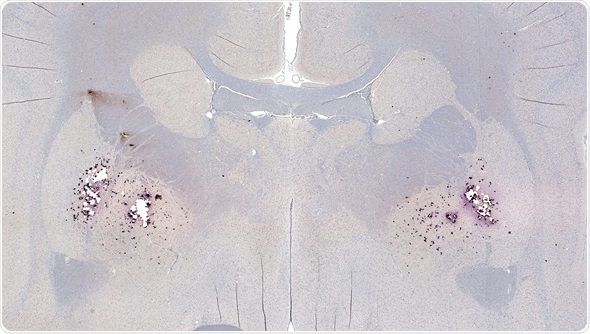

Amyloid plaques consist of dense, mostly insoluble clumps in the spaces between the nerve cells in the brain tissue. The plaques are made up of beta-amyloid, which is a protein peptide or fragment that appears to have toxic effects on the function of the surrounding brain cells.

Image Copyright: vetpathologist, Image ID: 73918573 via www.shutterstock.com

Over time, some individuals develop amyloid plaques in the central nervous system as they age. There are some regions of the brain that are particularly prone to the development of the plaques, such as in the hippocampus. The hippocampus is important for the processing of memories from short-term to long-term and damages in this area of the brain is associated with symptoms of Alzheimer’s disease.

The exact role of amyloid plaques in the pathogenesis of Alzheimer’s disease is not well understood. It is evident that they are more prevalent in individuals with the disease, but it is unclear if they cause or are a by-product of the disease. However, there is some evidence to support the suggestion that some genetic mutations lead to an increase in beta-amyloid production, responsible for causing some forms of Alzheimer’s disease.